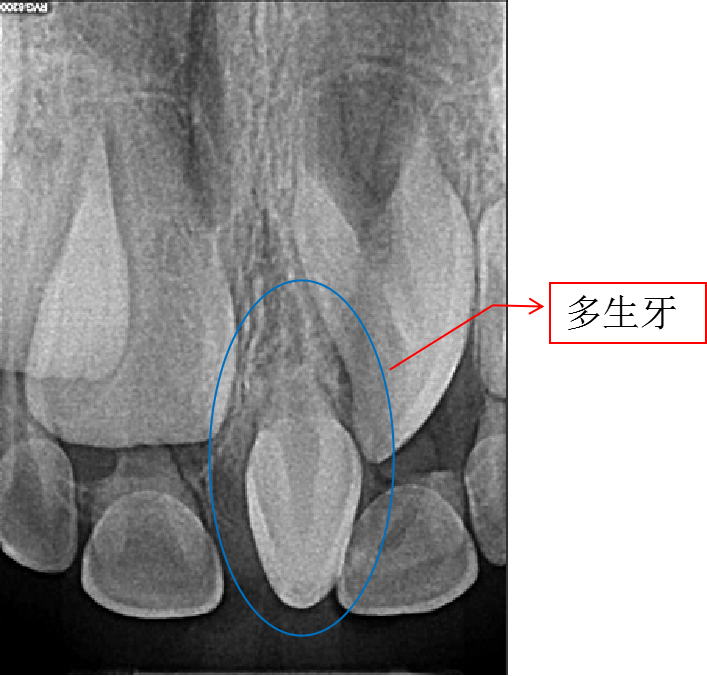

有时候肉眼无法判断,就需要拍摄X线片,辅助检查。

图片

上门牙间多生牙X线片

两颗本应该相邻的牙齿之间多了一颗牙齿,中间当然会出现缝隙。若是多生牙导致门牙缝隙,建议拔除多生牙后矫正关闭牙缝。